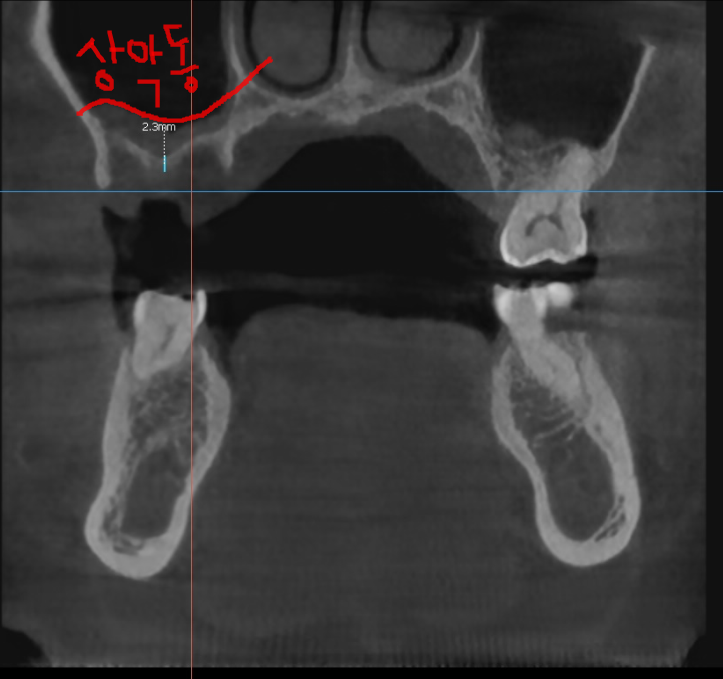

ct를 촬영해보니 한쪽 뿌리가 팔 뿌러지듯

골절 선이 보입니다.

치아 뿌리가 파절되면서 염증이 생기고

주변 잇몸뼈를 녹였습니다.

231121

잇몸뼈가 남아있는 양 옆 치아와 비교해보아도

유독 문제 치아 주변으로만 까만 것이 보이실겁니다.

뼈가 다 녹아서 그렇습니다.

240108

3개월 뒤 망월동 치과 재방문하여 찍어본 x ray

어느정도 잇몸뼈가 만들어지긴 하였지만

2.3mm의 길이만 확보되었습니다.

최소 6mm가 더 필요하여

2차 뼈이식을 진행하면서 임플란트를 심었습니다.